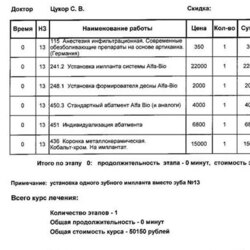

Врач предварительно подготовит полный расчёт стоимости и зафиксирует цену, ориентируясь на индивидуальные особенности вашего случая.

Врач предварительно подготовит полный расчёт стоимости и зафиксирует цену, ориентируясь на индивидуальные особенности вашего случая.

Врач предварительно подготовит полный расчёт стоимости

и зафиксирует цену, ориентируясь

на индивидуальные особенности вашего случая.

Врач предварительно подготовит полный расчёт стоимости

и зафиксирует цену, ориентируясь

на индивидуальные особенности вашего случая.